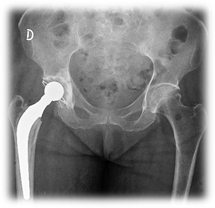

Parcial o total de cadera (Figura 4)

Paciente en decúbito contralateral al lado a operar. Se realiza abordaje posterolateral (Gibson). Fasciotomía, bursectomía, se identifican pelvirrotadores y se los secciona con electrobisturí. Capsulotomía en L o T. Se extrae la cabeza femoral. Se regulariza fractura, basicervical, con gubia. En un primer tiempo, si es un RTC, se trabaja el componente acetabular, con fresas crecientes, se prueba y se coloca componente definitivo (previo cementado para pacientes añosos). En un segundo tiempo o en el caso de un RPC, se trabaja canal femoral con raspas crecientes, se prueba prótesis, colocación de tapón óseo con tejido autólogo o sintético y se cementa la prótesis definitiva. Se reduce y se comprueba estabilidad. Cierre por planos.

Figura 4- Artroplastía parcial o total de cadera

Figura 4